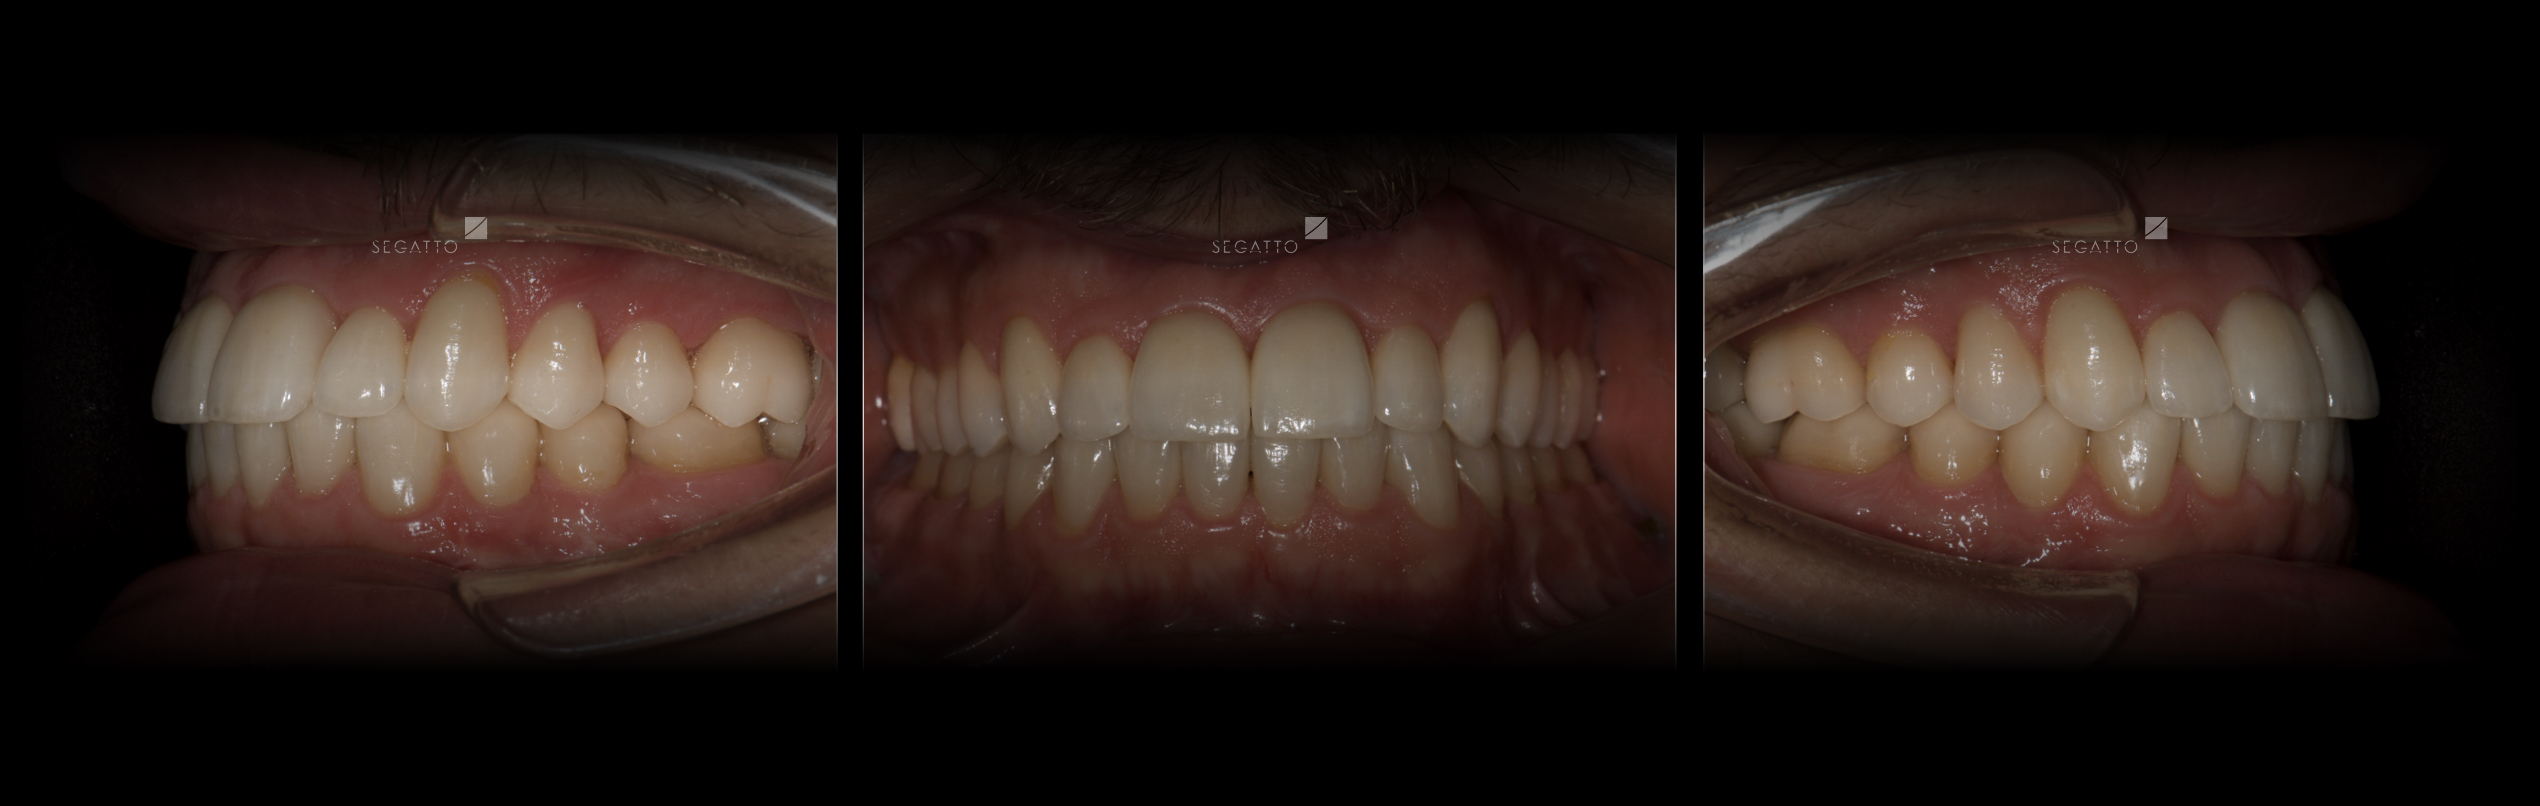

Orthodontics

Cases